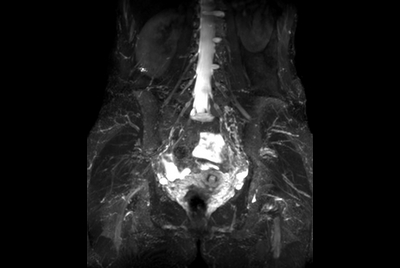

Push-button Lumbar Spine exam, under 5 minutes